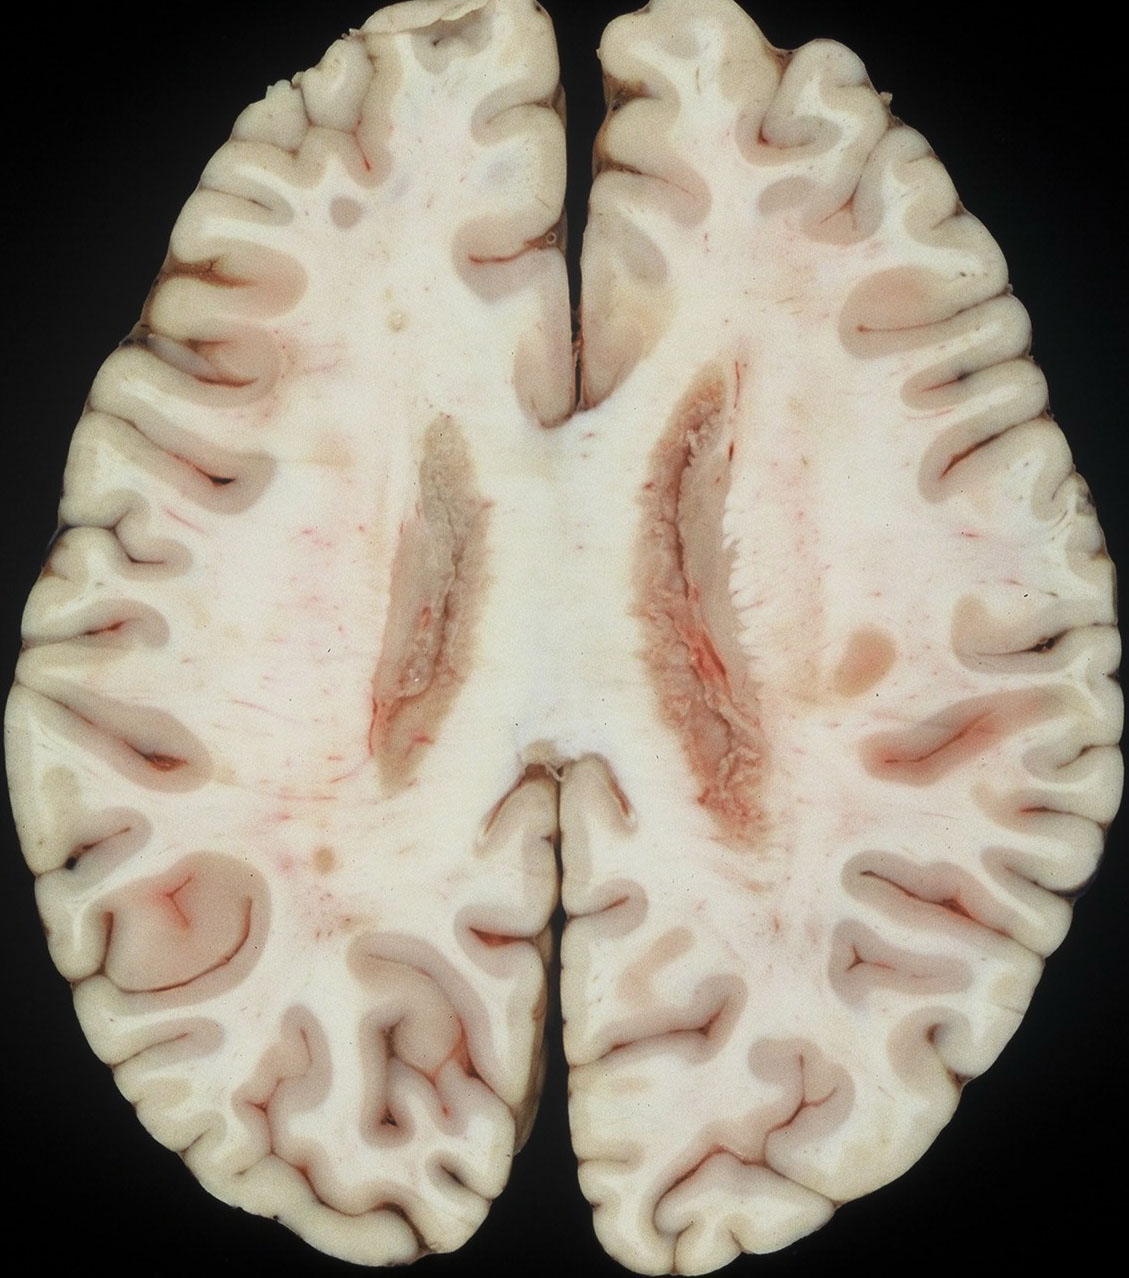

1992年の剖検所見

大脳表面,脳幹部,脊髄くも膜下腔には腫瘍が見当たりませんが,側脳室を充満するように腫瘍が増殖しています。

上方が側脳室側です。脳との境にある脳室上衣 ependyumの下に腫瘍細胞が這うように浸潤しています。そこから血管周囲 Virchow-Robin spaceを通って脳深部に浸潤しています。

大脳深部(左)と小脳深部(右)には髄質血管に沿って浸潤します。これは髄芽腫などと同様の脳浸潤所見です。